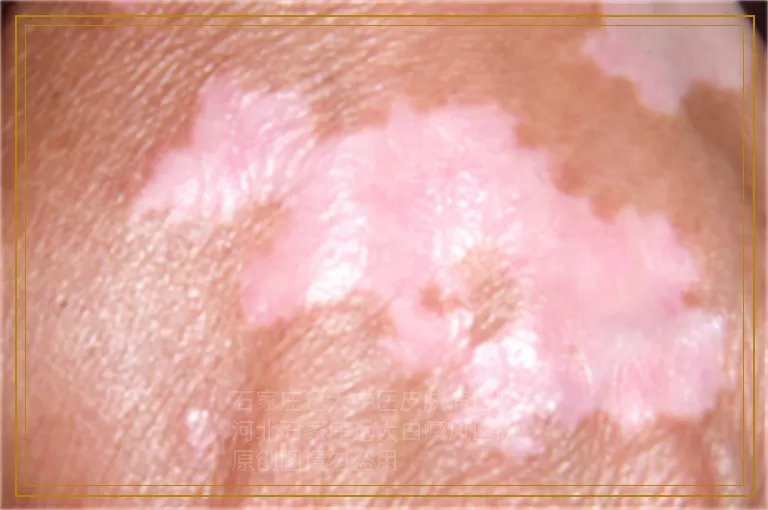

婴儿出现白癜风怎么治疗好

当新手爸妈在洗澡时发现宝宝胸前或脸颊冒出米粒大的淡白斑,心跳瞬间飙到一百八,其实门诊里这类“婴儿白癜风”七成是虚惊一场,要么是汗斑,要么是单纯糠疹,但确实也有极小比例是真性白癜风。三个月以内的小宝贝皮肤屏障还没长结实,任何外界摩擦、口水刺激、紫外线小剂量累积都可能诱发同形反应,让局部黑色素细胞“罢工”,所以第一步不是想着怎么治,而是先确认“是不是”。用手机把白斑拍下来,隔三天再拍一张,如果颜色越来越白、边缘越来越清晰,就要带娃去专科做woods灯,几十秒就能看清有没有荧光亮白,只要医生点头说“要考虑白癜风”,家长接下来要做的就是稳住情绪,别把焦虑写在脸上,小婴儿能敏感读到大人表情,一哭闹体内肾上腺素飙升,反而让白斑边缘更活跃。